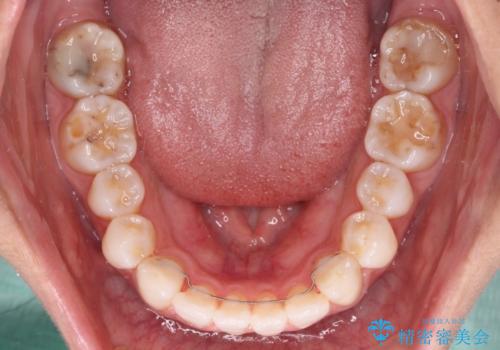

- 少しだけ前に飛び出ている前歯を気にして来院された患者様です。

上顎歯列全体を後方に移動させる必要があり、インビザライン単体での治療は困難と判断し、補助装置により左右側方歯列を移動させた後にインビザラインを用いることとしました。

インビザライン単独でも上顎歯列全体を後方移動することで臼歯の咬み合わせを改善できる場合もあります。しかしながら、矯正治療は当初設定したゴールに到達する必要があり、今回のような場合ではインビザライン単独では達成の可能性が低くなるので、補助装置を使用して、より確実に治療を行うこととしています。